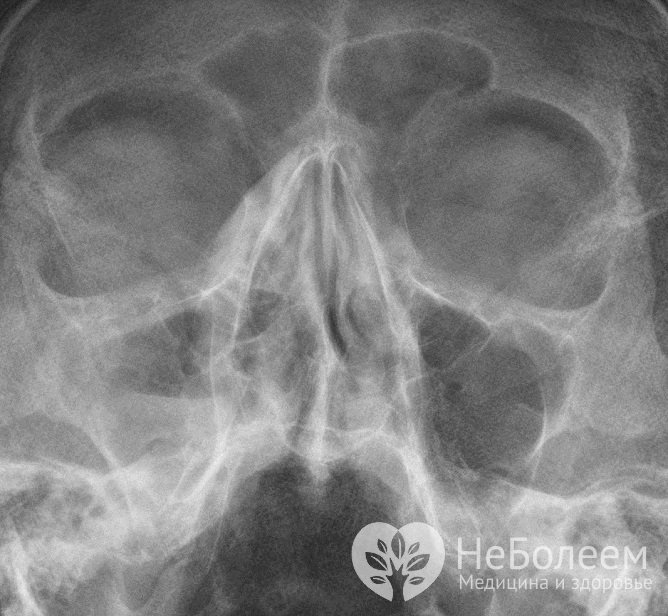

Важную роль играет рентгенологическое исследование околоносовых пазух носа. На рентгенограмме визуализируется пристеночный отек слизистой оболочки пазухи, гомогенное затемнение или наличие уровня жидкости в полости синуса при гнойном процессе.

С целью уточнения диагноза назначается рентгенографияВо время диагностики нужно учитывать, что возможны три варианта течения заболевания: